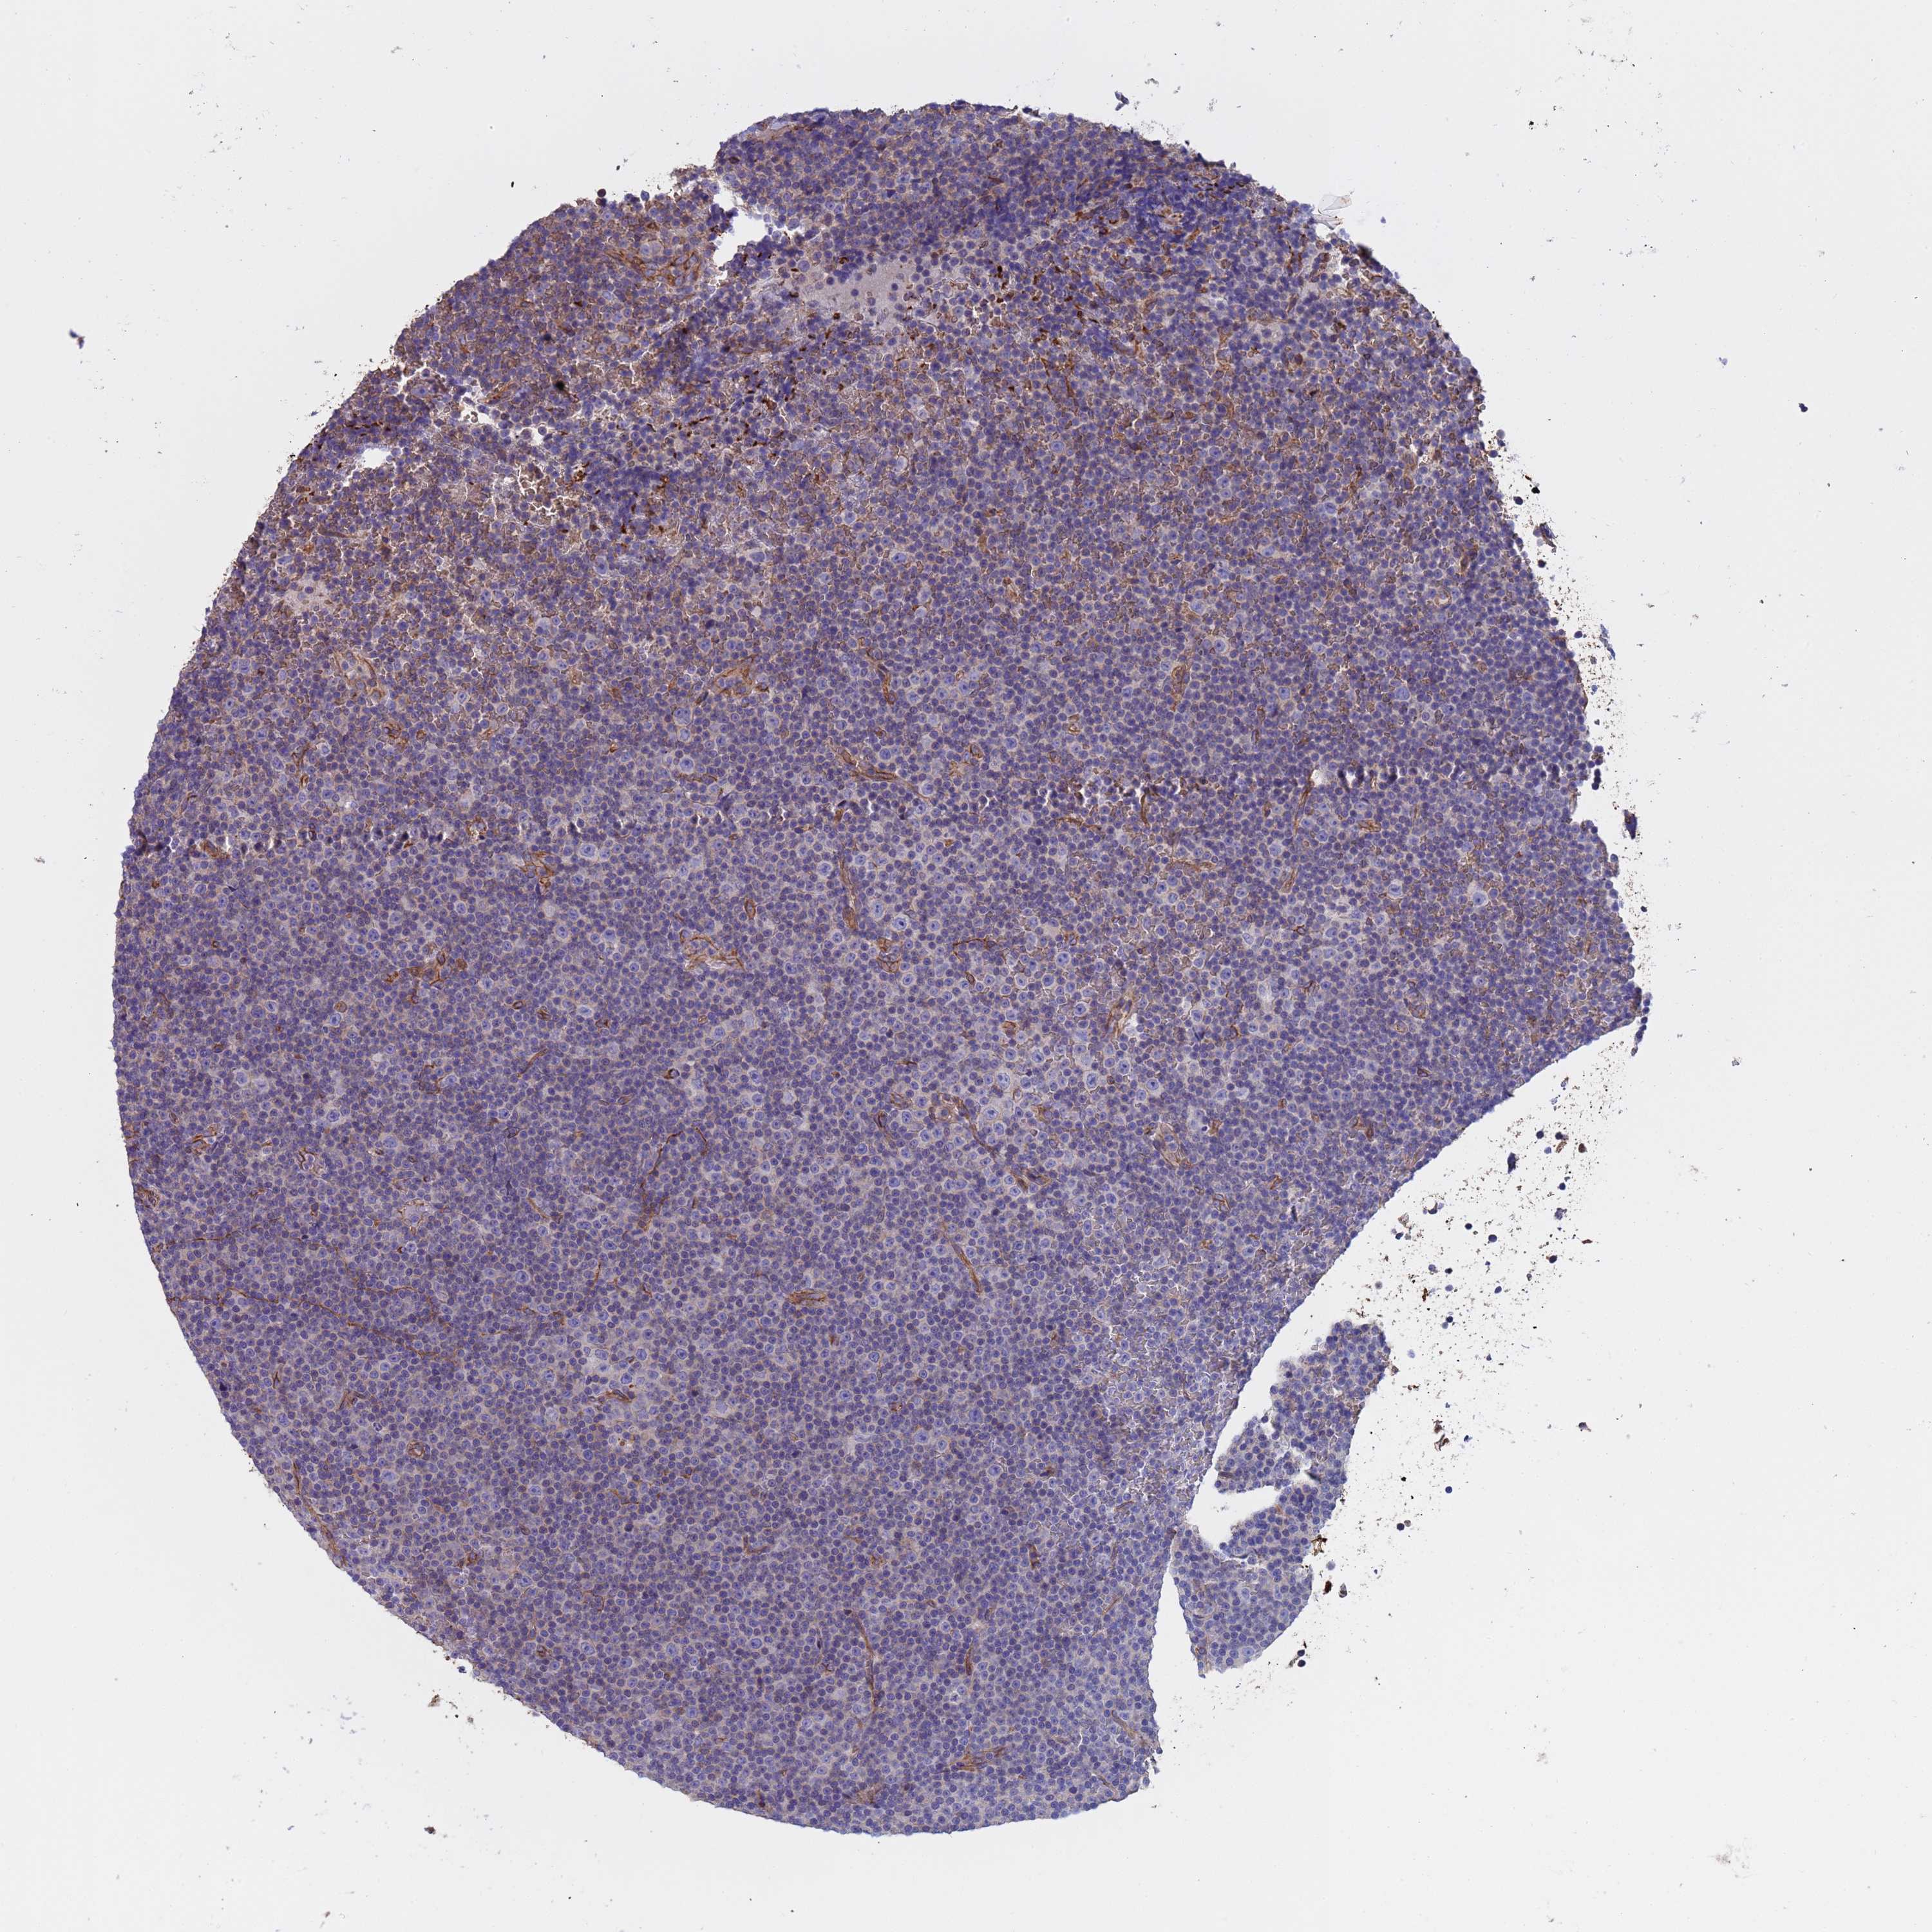

CANCER LYMPHOMA Show tissue menu

LYMPHOMA - Protein expressioni

A mouse-over function shows sample information and annotation data. Click on an image to view it in a full screen mode. Samples can be filtered based on level of antibody staining by selecting one or several of the following categories: high, medium, low and not detected. The assay and annotation is described here.

Each image is clickable and will lead to virtual microscopy that enables deeper exploration of all samples and also displays staining intensity scores, fraction scores and subcellular localization as well as patient and tissue information for each sample.

Antibody HPA018287

Hodgkin's disease, NOS

Malignant lymphoma, non-Hodgkin's type, High grade

Malignant lymphoma, non-Hodgkin's type, Low grade